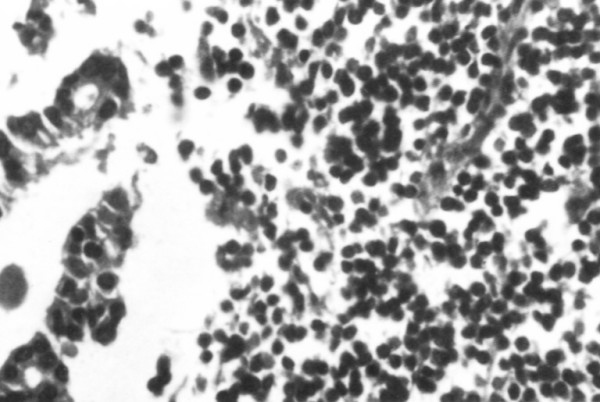

Subsequent pathologic examination of the removed lymph node showed total infiltration from a low grade lymphoma; with a limited metastatic infiltration from an adenocarcinoma noted in the same specimen (Figure 2).